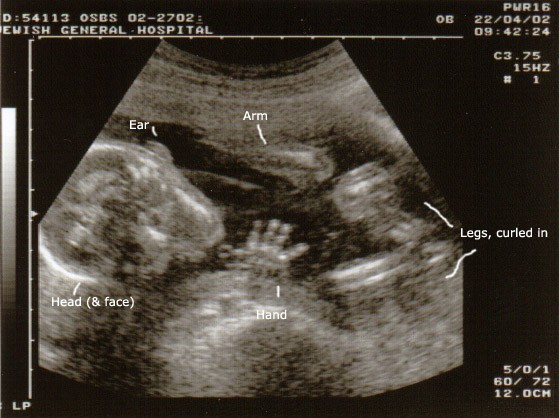

One year ago today, I saw my daughter for the first time. She looked like this:

wave

That was when we found out that she was, in fact, a "she". That was when we chose her name (well, names, since she has two middle names too). That was when it was surreal - even more exciting than hearing the heartbeat.